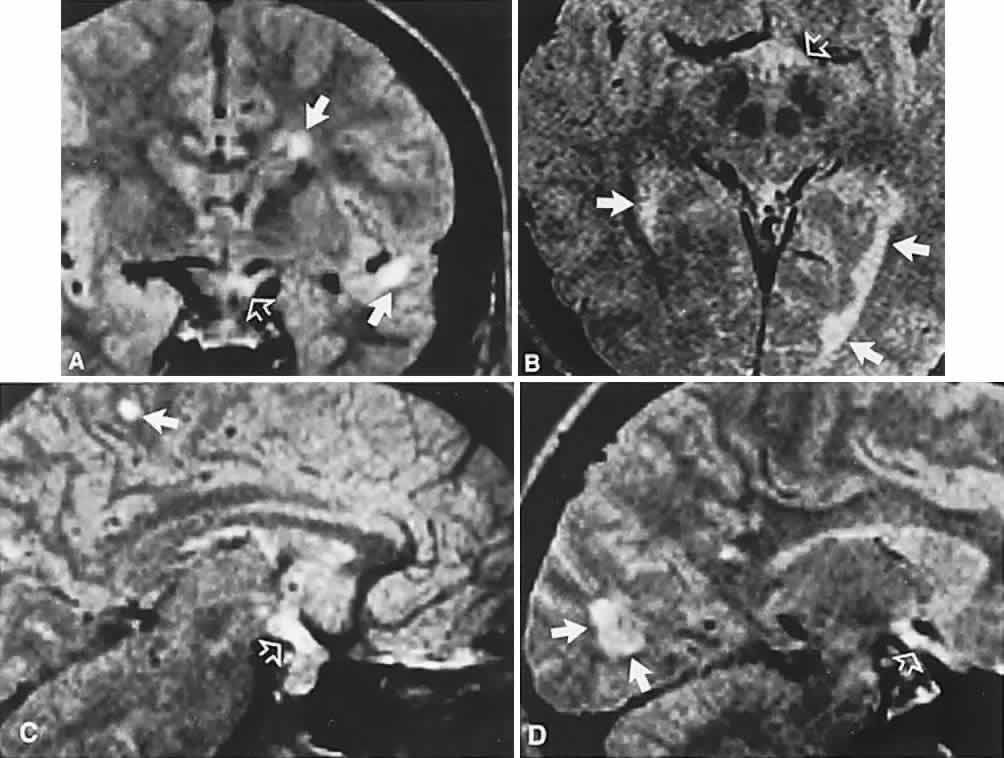

In previous decades, chiasmal interference with optic atrophy, but “normal” plain skull films, was referred to as “Cushing's syndrome of the chiasm,” caused by meningiomas, aneurysms, or other noncalcified suprasellar lesions. The modern neuroimaging techniques of enhanced CT, “bone-window” protocols, and gadolinium-contrasted MRI are now exceedingly sensitive in disclosing meningiomas or other parachiasmal masses (Fig. 4). At present, contrast-enhanced CT or MRI precisely demonstrate extra-axial tumor configuration; CT is superior in disclosing calcification or bone changes, but it is inferior for assessing suprasellar or intrasellar extension, postsurgical changes, and vascular displacement or encasement.76 Whether MRI or even MR angiography obviates standard selective arteriography, especially when surgical intervention is contemplated, is moot.

Fig. 4. Magnetic resonance imaging of a suprasellar meningioma (TR, 600 milliseconds; TE, 20 milliseconds). A. Coronal section of a large meningioma (large arrows), isodense to brain. B. Sagittal section. Note the normal sella and pituitary gland (p). Sagittal (C) and coronal (D) sections of a planum meningioma, extending into the sella. Note the upward deflection of the chiasm (arrow in C) and extension to the cavernous sinus (arrows in D).